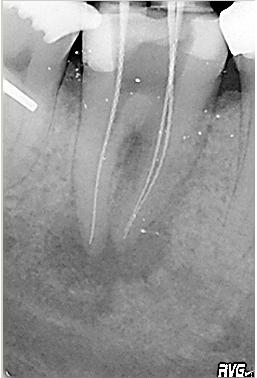

Röntgenmessaufnahme

Röntgenmessaufnahme im November 2002 nach vorgängig durchgeführter endometrischer Längenbestimmung. Zuerst erfolgte der adhäsive Aufbau des Zahnes mit anschließender Trepanation